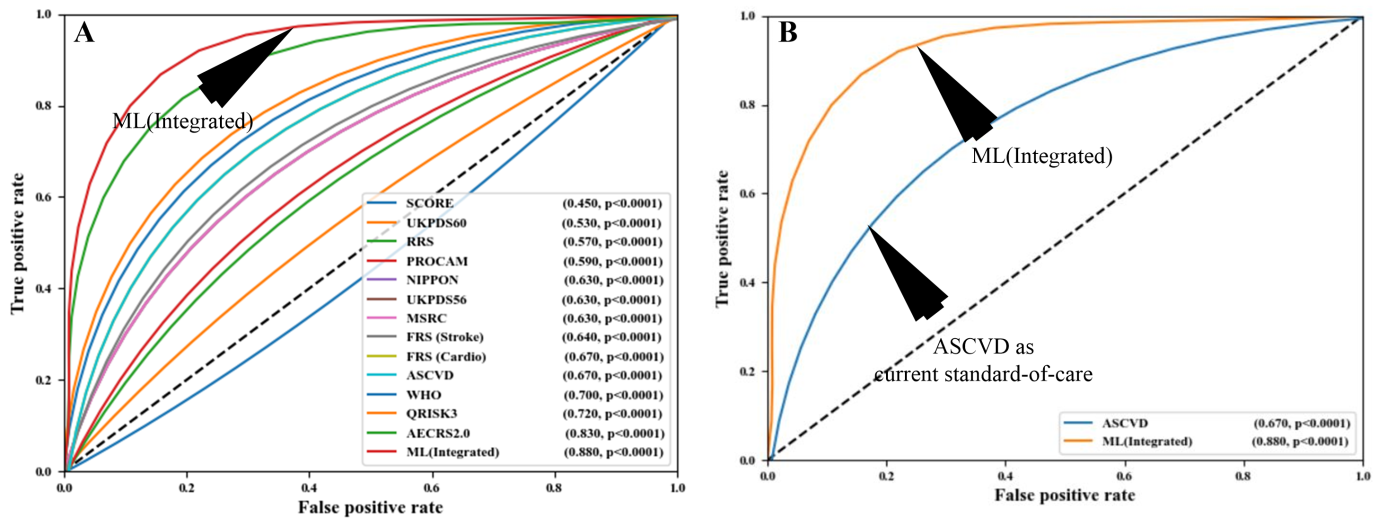

Another study by Weng et al. [185] also supported the outperformance of AI-based algorithms over the PCRE for CVD risk assessment. Knowing that the integration of carotid ultrasound image-based phenotypes can provide better CVD risk assessment, Jamthikar et al. [130, 186] presented a study to compare the AI-based algorithm against the 13 different types of CCVRC for CVD risk assessment (Fig. 10, Ref. [186]). In their study, AI-based algorithms showed an overall risk-stratification accuracy of 92.52%, which was higher compared to all the 13 types of CCVRC. The authors also showed the role of machine learning for better risk prediction that used carotid ultrasound plaque characteristics to improve the risk stratification accuracy [187, 188]. The same authors also supported their claim of superiority of AI-based algorithm over CCVRC in a recent study that predicted multiclass risk profile in Canadian patients [140]. A comparison between AI-based vs. statistical-based calculators can be shown in Fig. 10 [186]. Such ML-based strategies for office-based settings are now available [31].

Fig. 10.

Fig. 10.Comparing the ML-based CVD risk assessment with conventional calculators. (A) Comparing ML-based system with 13 types of CCVRC and (B) comparing ML with the standard-of-care ASCVD calculator (Reproduced with permission [186]).